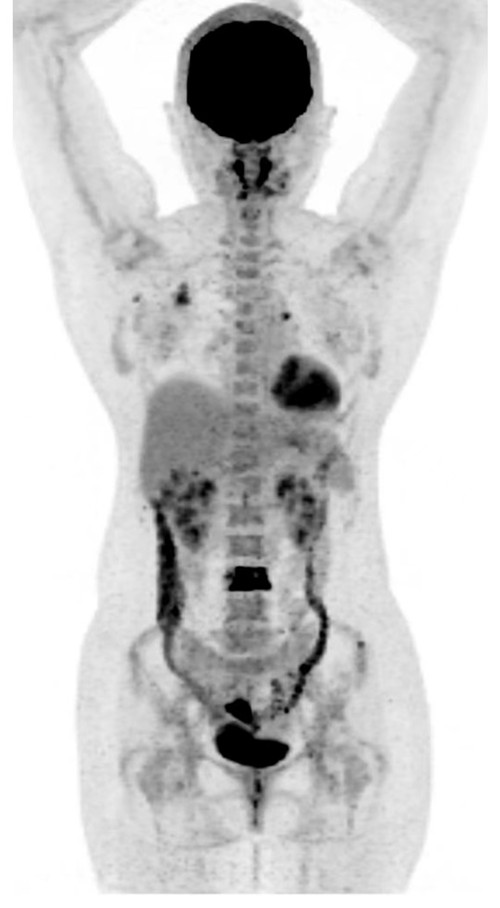

PETCT显示右侧乳腺内糖代谢明显增高的结节和腰椎的转移癌

问题来了,彭女士腰椎转移癌原发灶在哪里?是甲状腺癌吗?因关系后续治疗方案,在医生的建议下,彭女士到捷克论坛 PET影像中心进行PET/CT扫描。检查结果让人大吃一惊,彭女士的右侧乳腺有一个糖代谢明显增高的结节,大小为10mm,高度提示右侧乳腺癌。这下解开了腰椎转移癌的谜底,乳腺癌除腰椎骨转移外,同时发现右侧腋窝淋巴结和骨盆多骨的转移。目前,彭女士已经转入乳甲外科接受手术及进一步治疗。

捷克论坛 PET影像中心主任毛志群介绍,相当一部分癌症在患者有症状时就出现了转移,全身PET/CT检查往往能快速发现原发恶性肿瘤,为临床病理的精准诊治提供极为重要作用,避免患者因做多个检查而花费更多时间和金钱,甚至延误治疗时间。对于肿瘤标志物升高的患者通过PET/CT全身检查可以尽早发现、明确诊断,从而获得更多的治愈机会,全身进行一次检查就可以发现癌变器官。PET/CT检查对于肿瘤分期具有非常重要的意义,可以直接为临床治疗手段的选择提供依据,甚至改变治疗方案。此外,PET/CT也是各种恶性肿瘤术后监测的利器,尤其是血液系统恶性肿瘤。